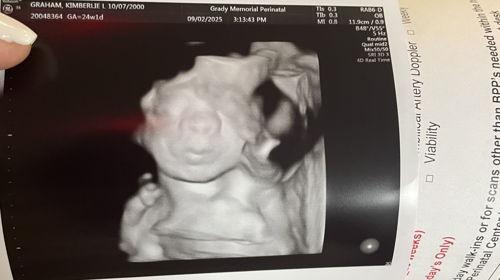

Arrival date December 22, 2025

Hey my name is kim I wanna start off by saying anything that anybody get me I am grateful for in I wanna say that im going into the pregnancy by myself in im happy for it that im having a baby girl